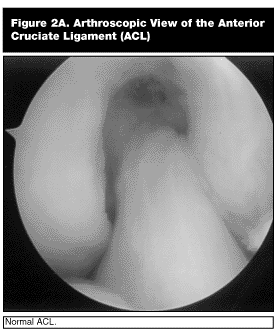

There are a number of ways to surgically reconstruct the ACL. Most ACL surgery is done with arthroscopic assistance using a variety of ACL grafts. These include autograft tissue such as patellar tendon, hamstring tendons, and quadriceps tendon or allograft tissue such as patellar tendon, hamstring tendon, or Achilles tendon.9,14 (See Figures 2A-C.) Following reconstruction, a rigorous physical therapy protocol of 4-6 months or more is essential in order to optimize the final results.9,11